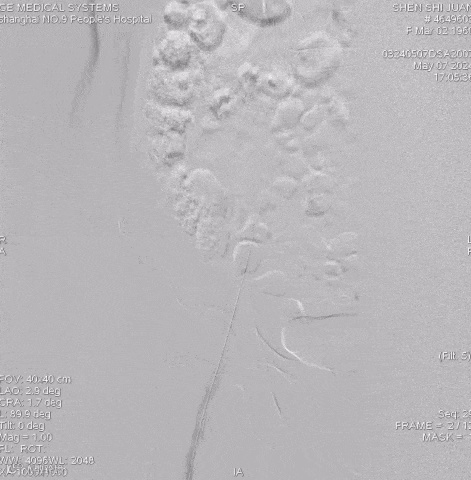

手术过程

抽吸结果